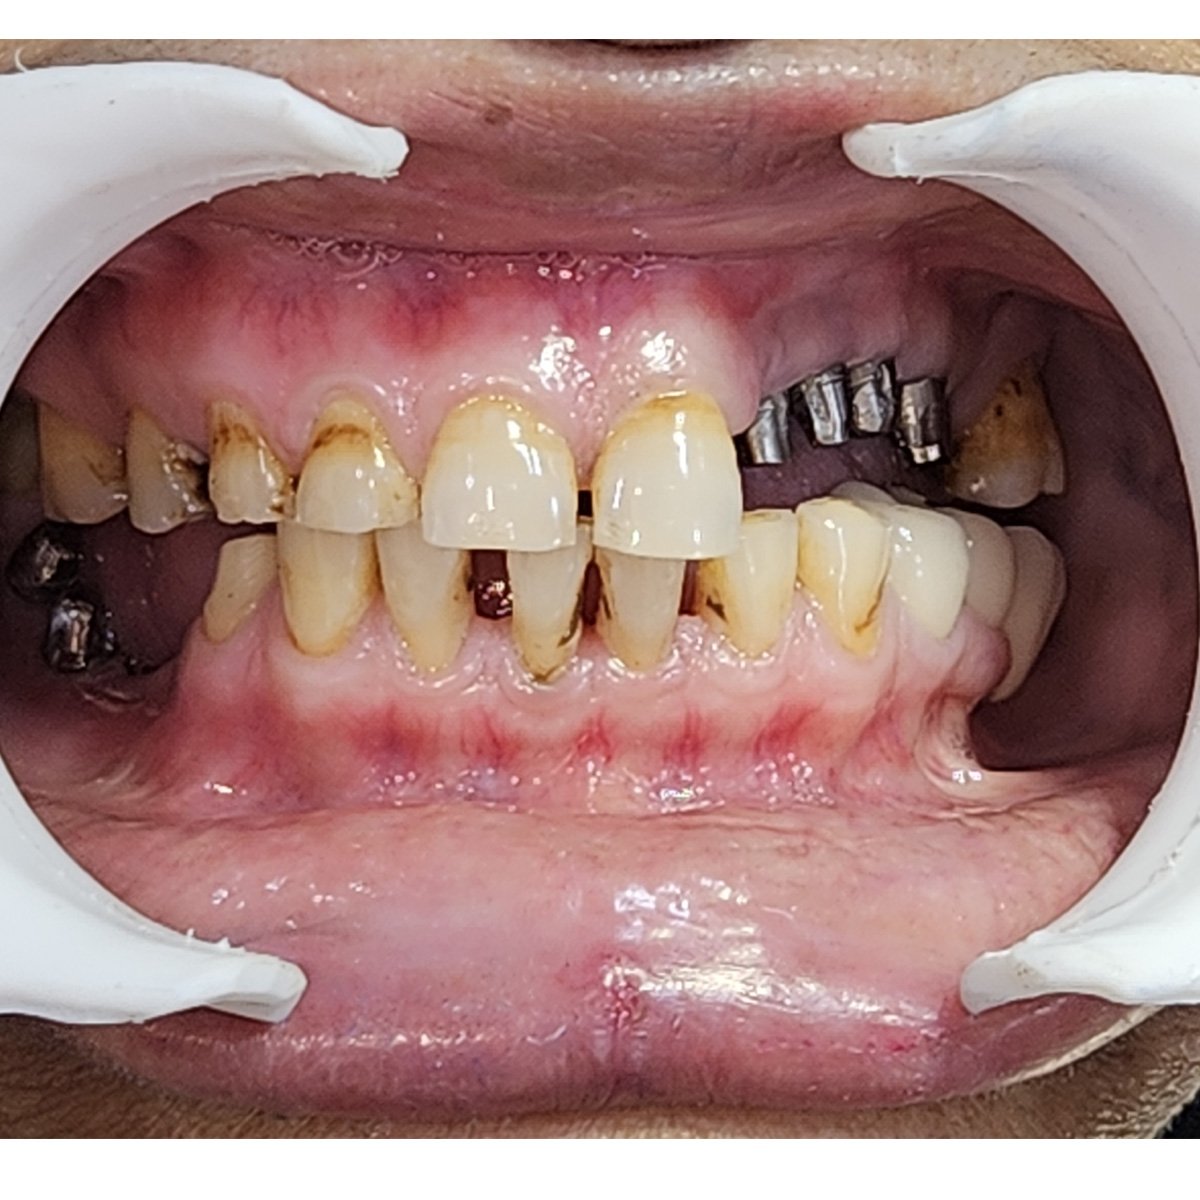

Case-10 Basal and compressive implants – segmental Restoration

Dr. N.B. Singh